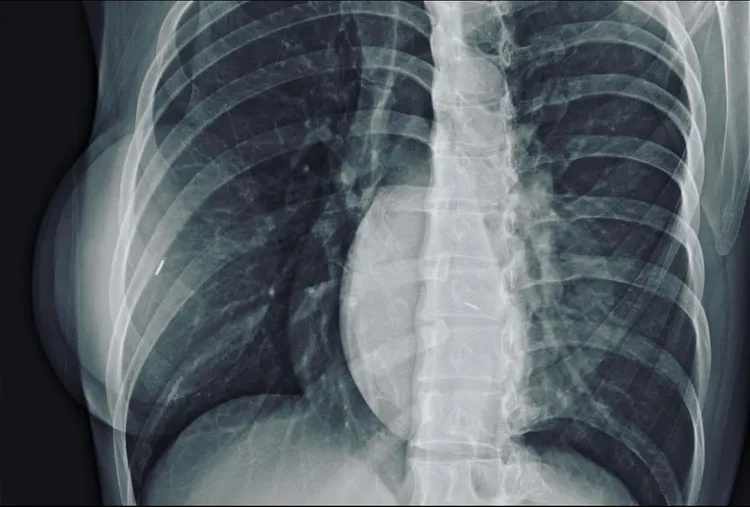

有網友貼出一名隆乳女性X光照,指「真奶不會出現球狀物體」。翻攝臉書爆廢公社

有網友在臉書爆廢公社PO出一張女性X光照,影像中左、右兩側各有兩顆灰白的球狀物,並加註「看到某女生勇於承認!」「要知道自己的女神/女友是否真假,帶她去做胸部X光檢查,圓球白影是代表她是假的,真奶不會出現球狀物體。」

高雄市立大同醫院整形外科主任賴雅薇看了這張X光照後指,這名女性確實是有做過隆乳術,植入的應是果凍矽膠。